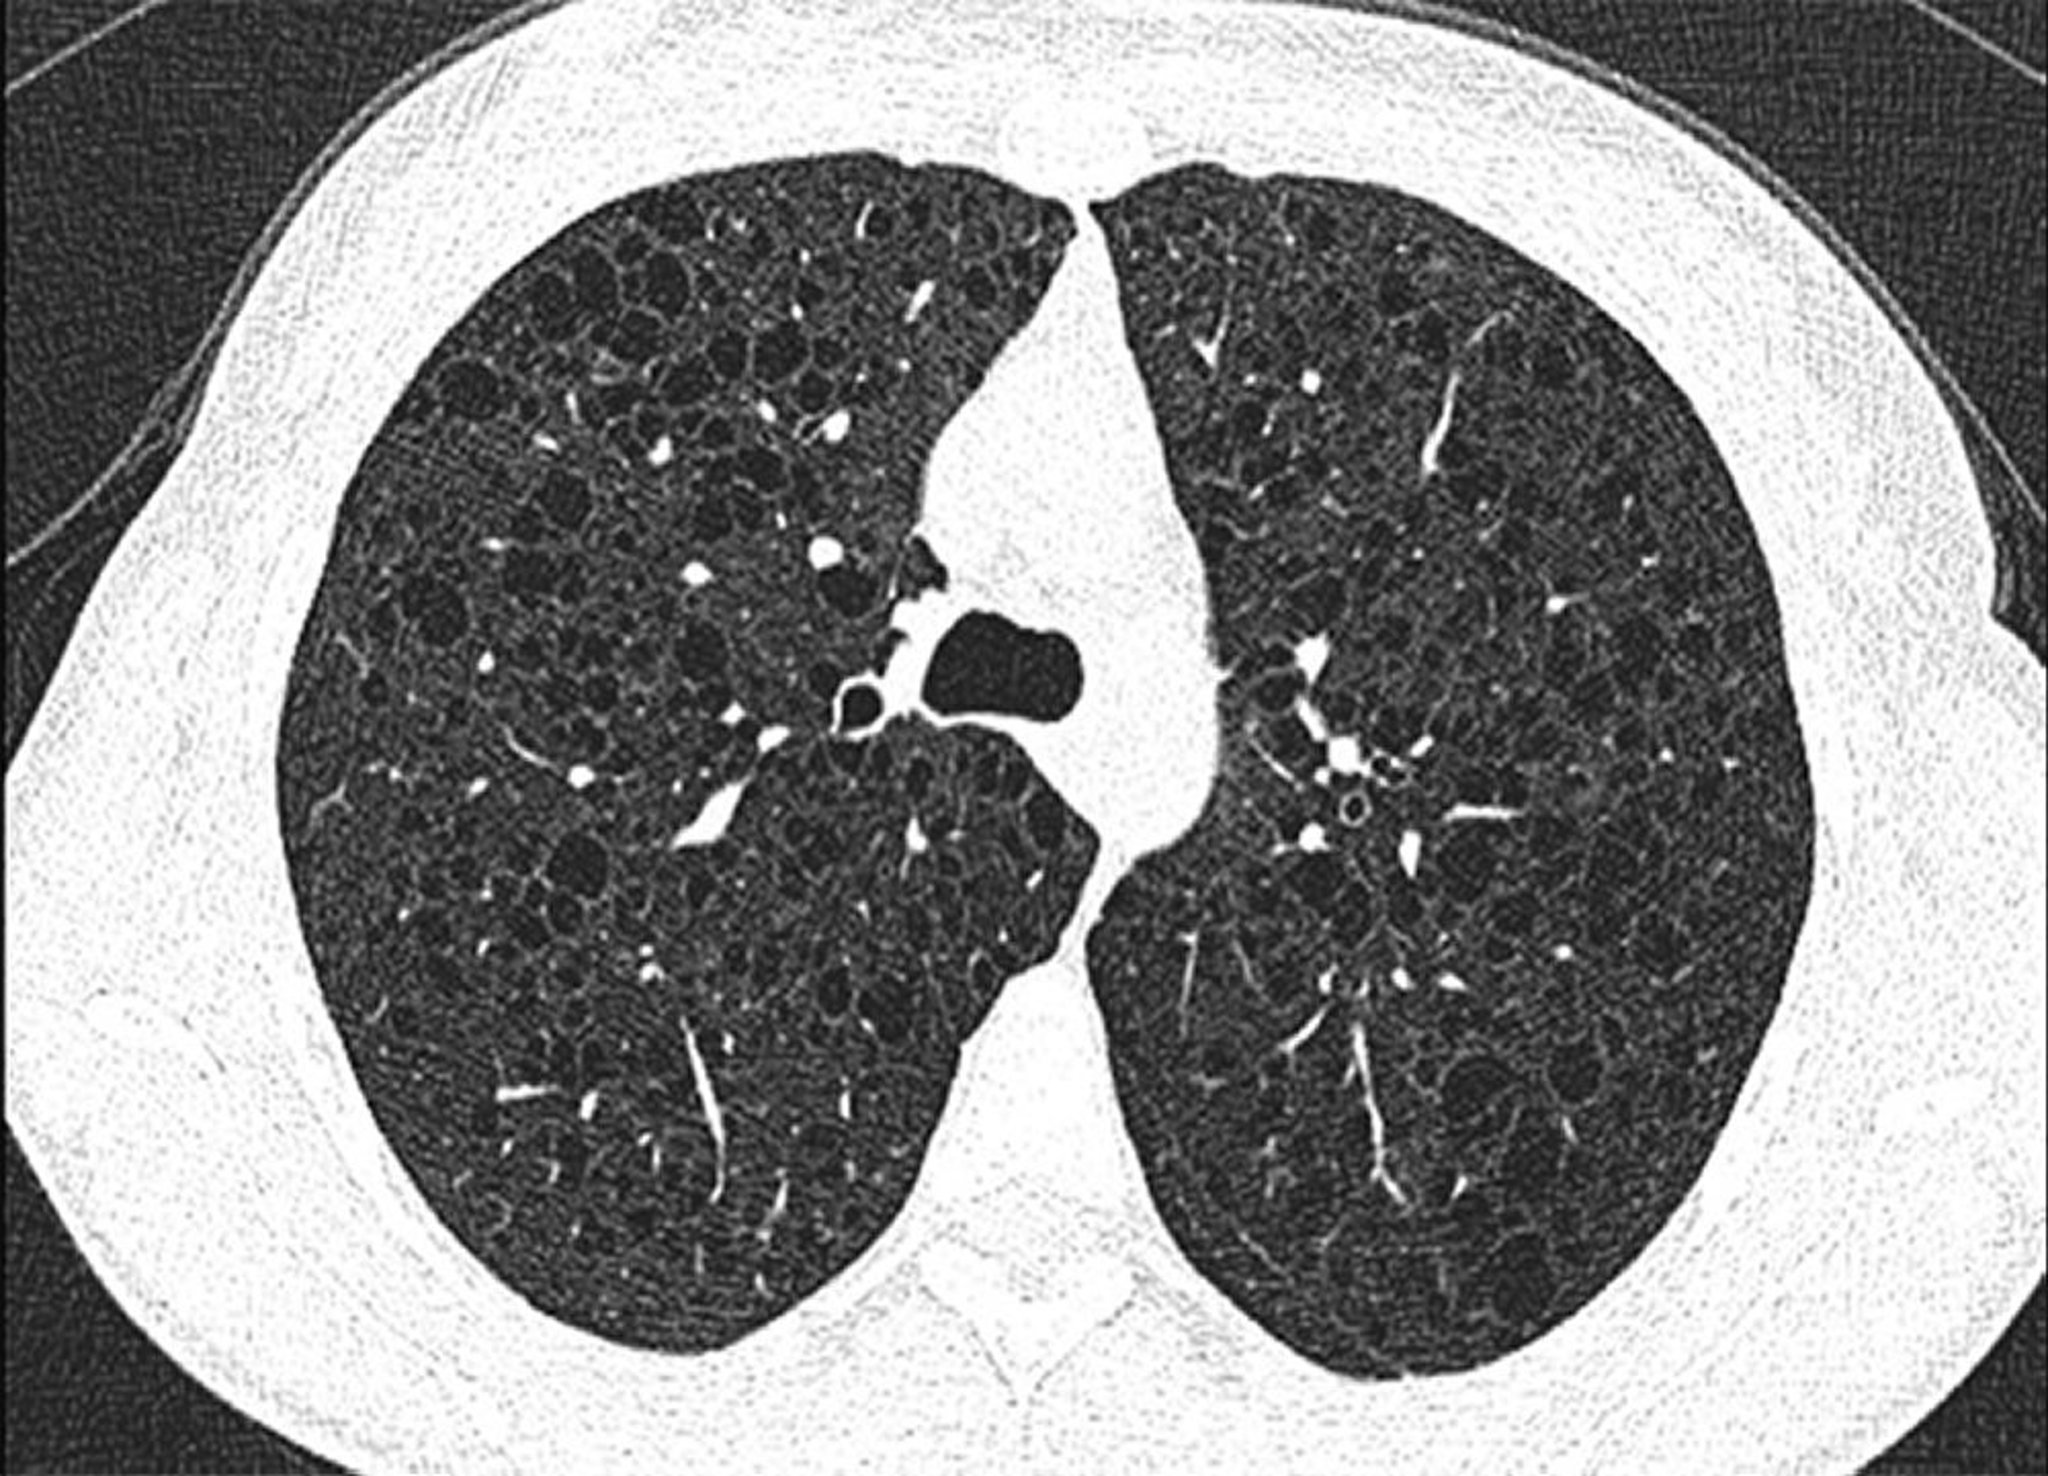

Esta imagen muestra quistes difusos en ambos pulmones en un paciente con linfangioleiomiomatosis.